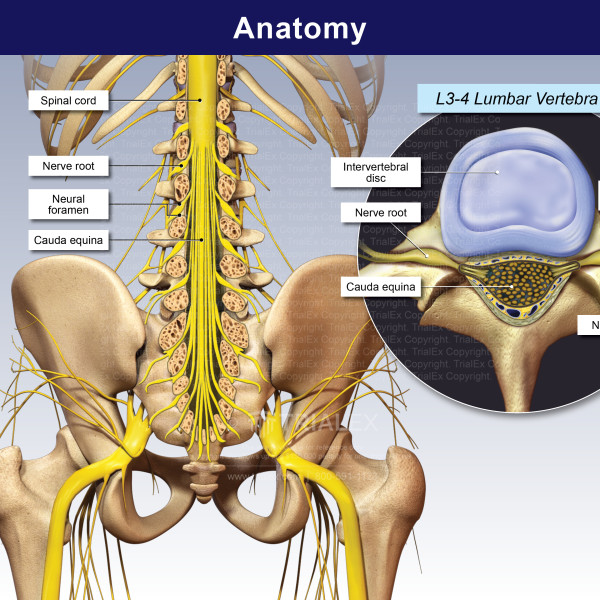

Lumbar Spine – TrialExhibits Inc.

Anatomy of the Lumbar Spine – TrialExhibits Inc.